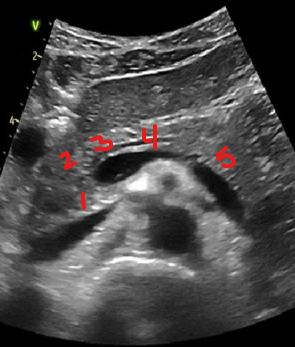

Identify this image.

Uncinate process

Pancreatic head

Pancreatic neck

Pancreatic body

Pancreatic tail